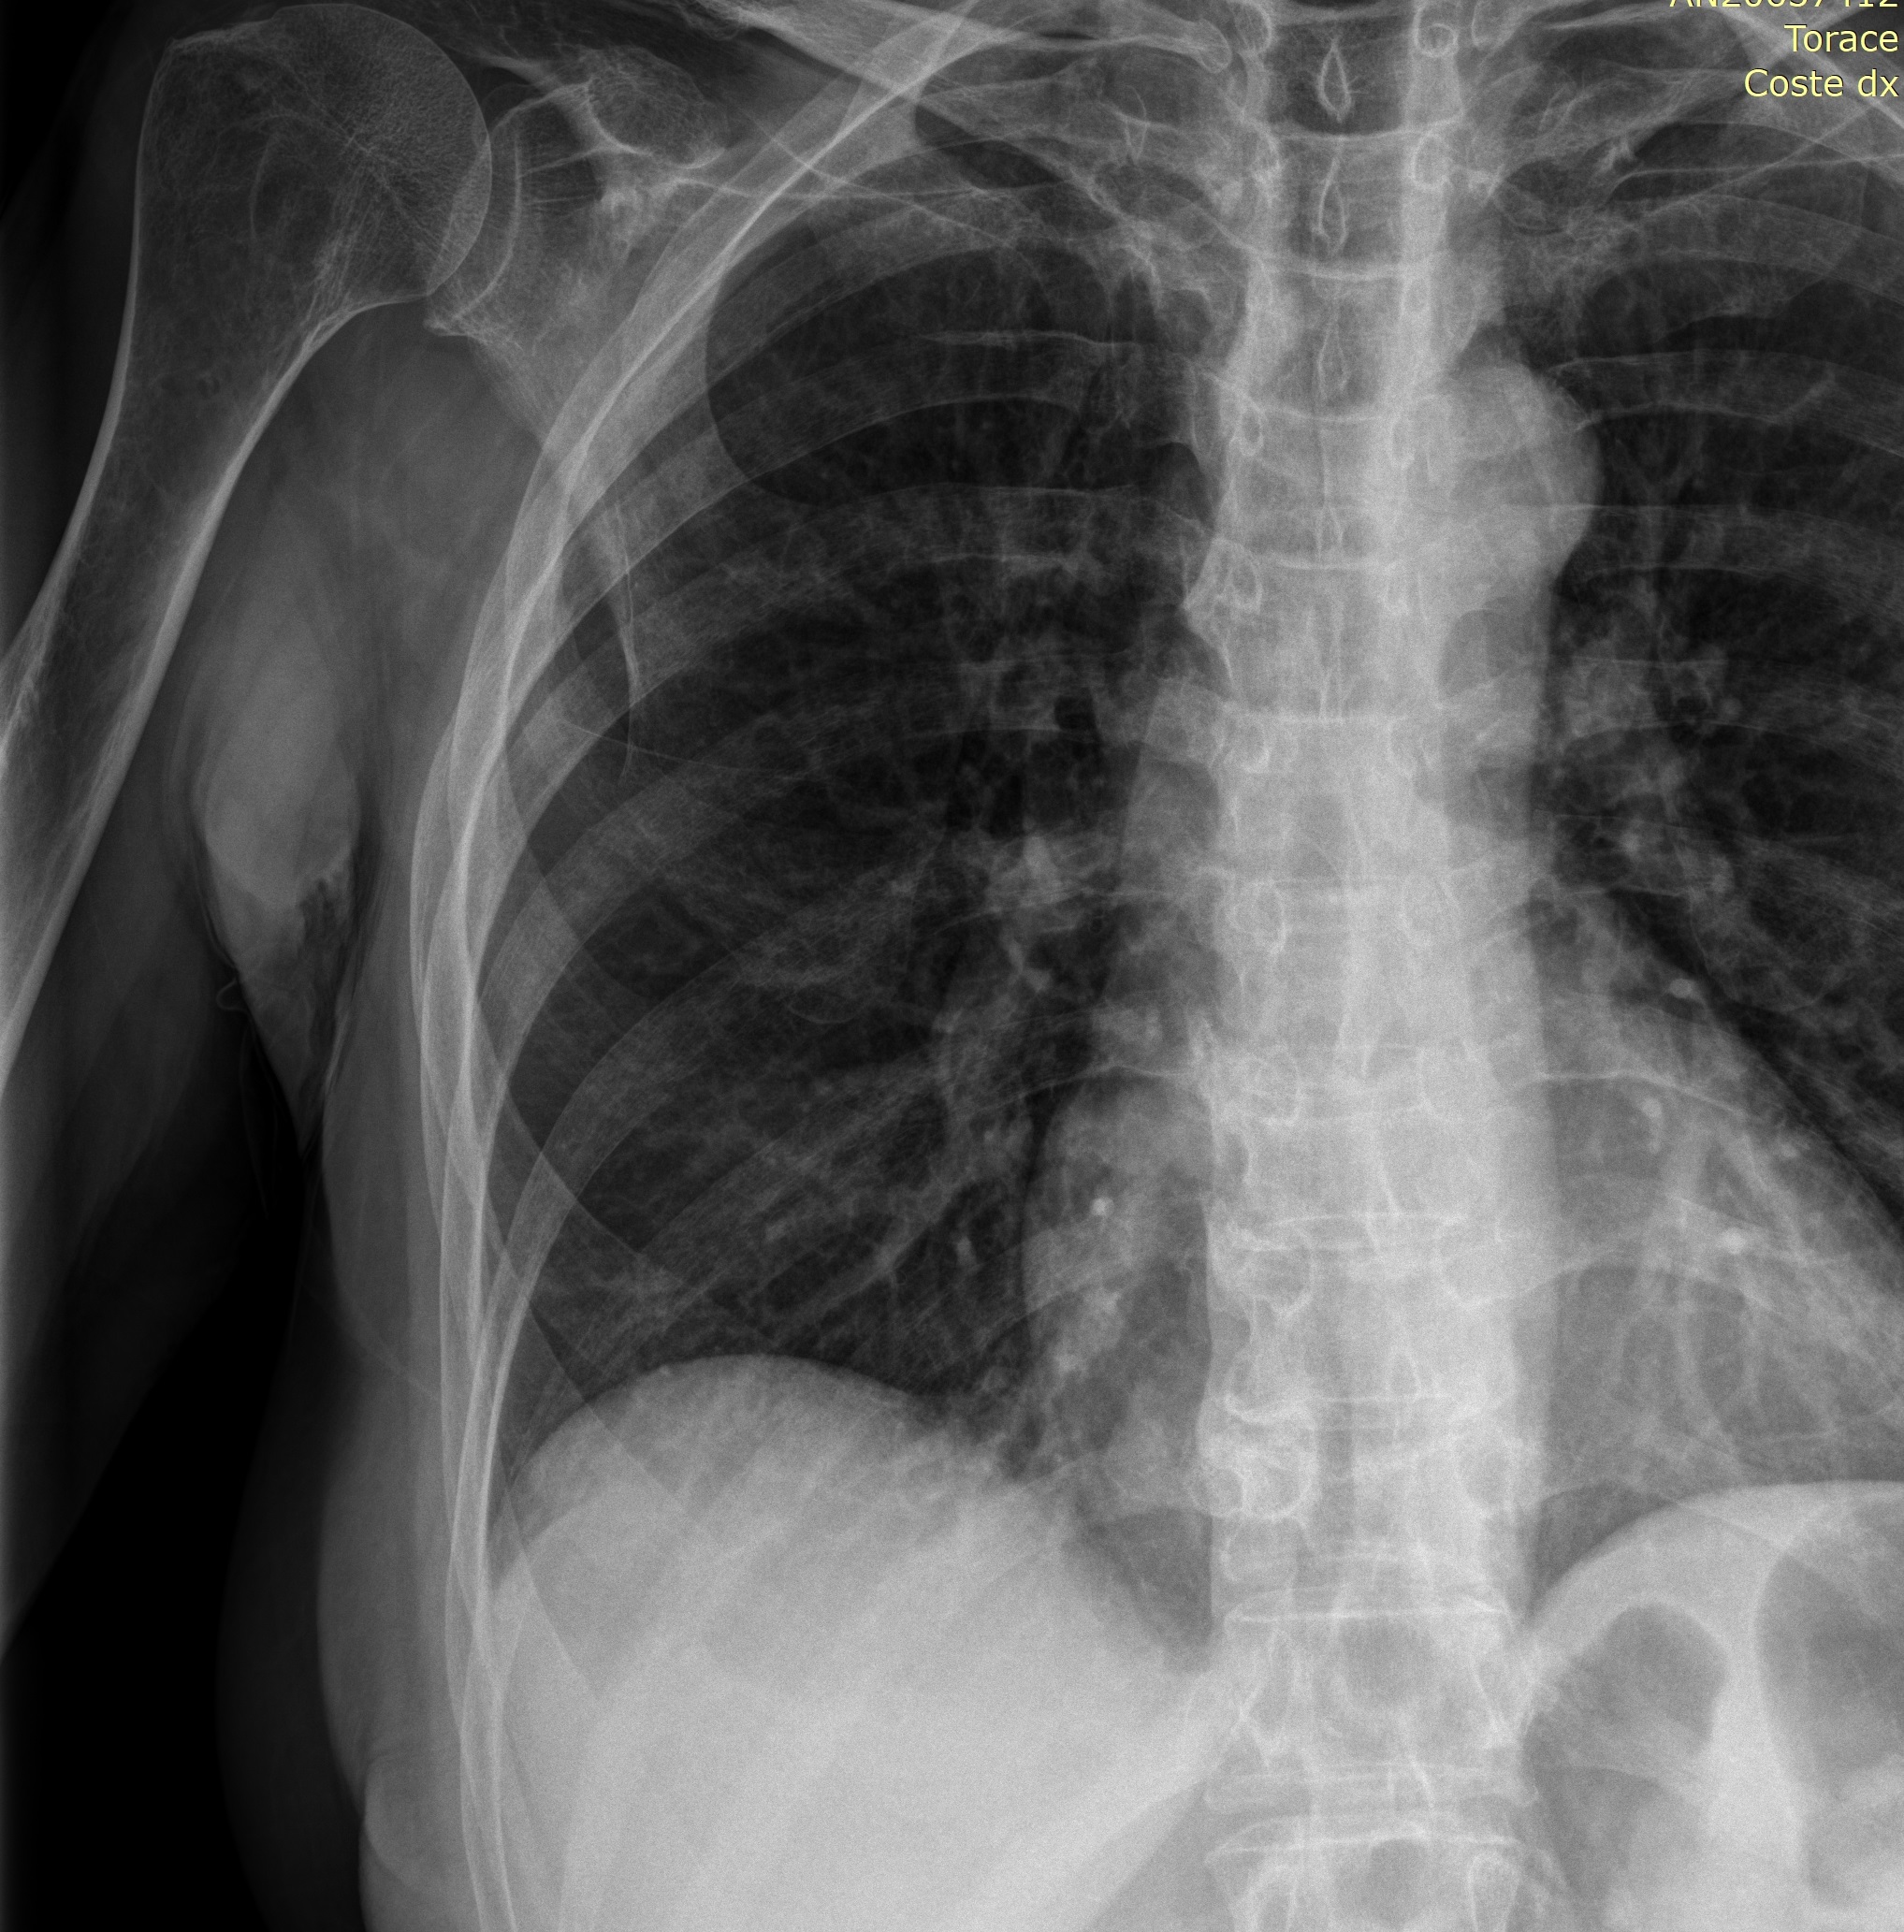

Caso di infrazione costale dx associata a frattura vertebrale di D9 formatasi nel medesimo infortunio (in associazione ad una pregressa frattura vertebrale di D11 consolidata) passata misconosciuta al primo esame radiografico, più precisamente interpretata come alterazione artrosica e valutata con semplice esame clinico, invece che con RMN (effettuata dopo soli tre mesi).

La domanda andrebbe rivolta a un radiologo. Posso però segnalare che la radiografia è una rappresentazione in due dimensione di un distretto tridimensionale, quindi esiste il rischio di perdere delle informazioni a causa della sovrapposizione di diversi tessuti/organi..